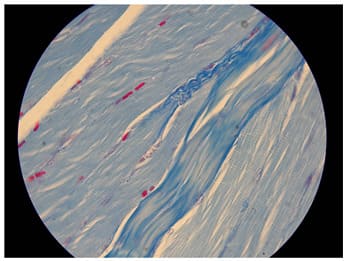

It is also clear that the tendinous system (tendons, endomysium and perimysium) is a continuous structure with no junctions. It is important to notice that the tendinous system is the structure that tears first in stretch-type injuries therefore one should follow the tendinous system to detect a tear. Ultrasound is a method of choice in this type of diagnostics. It only takes some effort to learn all the muscles tendinous systems anatomy. The end (cone) of the myofiber shows interesting feature of the tendinous system. At the level of the cone longitudinal striations can be seen on longitudinal/oblique sections (Figures 8,9,10). This phenomenon can be explained in only one way. This is where the loose connective tissue covering the whole myofiber must compress to single fibers of compact connective tissue and further on the tendon. It looks as they compress forming thin bands of tendon which gradually become a solid tendon. Therefore the end of the myofiber (the cone) is a transition zone from loose to compact connective tissue. At the cone level despite the parietal myotendinous junction there is another myotendinous junction mechanism. Actin filaments are anchored from one side to the Z-membrane, from the other side instead of interlacing with miosin penetrate through sarkolemma to the extracelular matrix just like integrines - also a parietal MTJ. Transverse sections of the muscle show that bands of endomysium are every few myofibers strengthened by bands of perimysium (Figures 11,12).

On Figures 13,14,15 examples of Azan stained specimens showing what perimysium does to the muscle’s tendinous system structure. During the process of contraction myofiber ripples as do many worms (Figure 16). The difference between a worm and the myofiber is that the worm contracts and relaxes its segments to crawl and the myofiber contracts at the whole length to shorten and bring the origin to insertion generating movement or create a desired position. It is worthy to notice that according to Gray’s anatomy [3] a human sarcomere is approx. 2 mm long in the relaxed state (1mm=1x10-6m=1x10-3mm). That means that a human myofiber has 500 levels of PMTJ for every milimeter of its length. An interesting feature of a myofiber is that the only myofibrills that transmit force directly onto endomysium (that is forming a PMTJ) are those which are peripheral. All other myofibrils transmit their force onto PMTJ indirectly through neighboring myofibrils and at the ends (the cone) of the myofiber. At the cone of myofiber all four types of nerve endings are seen: Ruffini and Vater-Paccini corpuscules, Golgi apparatus and free nerve endings [4] This fact proves that the cone is a key proprioceptive zone of the myofiber.